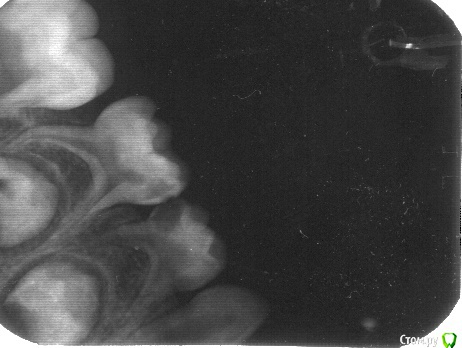

Kukkolos Опубликовано 8 июня, 2015 Поделиться Опубликовано 8 июня, 2015 Здравствуйте, уважаемые профессионалы.Лечимся в госклинике. У сына (4,5 года) пульпит 4 -го нижнего зуба справа: жаловался,что зубик болит при жевании. Сын заболел ОРВИ с высок. темп., в день, когда было назначено лечение прийти не смогли. Пришли спустя 4 дня в четверг: врач предложила отложить лечение, т.к. оно проводится в несколько посещений, а она уходит в отпуск в пн. и не сможет долечить. Спрашивала меня: ну, что, все-таки будем начинать? Я решила: начинать, а долечивать с другим врачом, т.к. записаться трудно. Направила в хирургический кабинет делать анестезию. Спустя 5 мин. наша врач решила зуб удалять, аргументировав это тем, что корень не длинный, что боится, что щеку разнесет после первого вмешательства, что спасая молочную четверку мы можем испортить коренной. Но сказала, что наше право выбирать: удалять или оставлять, при этом в карте написала, что зуб лечению не подлежит. Еще сказала, что мы можем пролечить зуб в платной стоматологии (они возьмуться лечить все, что угодно), но это не гарантирует положительный рез-т. И в итоге: все-равно зуб нужно будет удалять. Хирург потрогала зуб: он не шатается, сказала, чтобы мы шли домой еще посоветовались с профессионалами. Мы ушли домой подумать. В настоящее время (спустя 4 дня после визита к врачу): зуб не шатается, не болит, десна спокойная. Помогите пожалуйста принять правильное решение: лечить зуб в частной клинике (в государственной не будут, т.к. в карте написано, что лечению не подлежит) или удалять? Снимок во вложении. Также интересует вопрос: пломбирование каналов молочных з-в мешает дальнейшему прорезыванию коренных? В каком возрасте нужно будет удалить запломбированную 4-ку? Ранее удаление 4-го молочного зуба может негативно повлиять на рост коренных. Стоит ли лечить в частной клинике в одно посещение или это вреднее, опаснее, чем в несколько? К чему стоит быть готовыми? Благодарю за оперативные ответы! Ссылка на комментарий

Джима Опубликовано 9 июня, 2015 Поделиться Опубликовано 9 июня, 2015 Я бы лечила. И пятёрку заодно. По вопросам:1. Если каналы запломбированы рассасывающимся материалом - нет, не мешает.2. Если с другой стороны абсолютно здоровая четвёрка сменится, а эта даже шататься не будет. Или если сбоку начнёт прорезаться постоянный зуб. Если будете наблюдаться раз в полгода у адекватного детского - не пропустите, не переживайте. Вообще, зубы у парня, по-видимому, ранние. Года через 3 этот зуб должен сам уйти, несмотря на лечение. Это будет слегка преждевременно, но лучше, чем сейчас.3. Количество посещений, а также все животрепещущие вопросы, лучше обсудить с реальным врачом.Удачи. Ссылка на комментарий

Kukkolos Опубликовано 10 июня, 2015 Автор Поделиться Опубликовано 10 июня, 2015 (изменено) Джима, благодарю за ответ! Я так понимаю, что в Нижнем Новгороде? Ищу врача в Москве, кто бы за это дело взялся. Вчера в одной платной детской стоматологии доктор сказала, что имеет смысл удалять, что корни рассосались почти... Есть ли у кого-то знакомые московские детские стоматологи, которые умеют пломбировать молочные каналы? Изменено 10 июня, 2015 пользователем Kukkolos Ссылка на комментарий